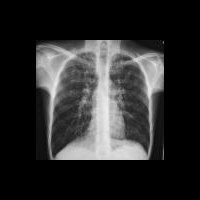

– Это генетическое заболевание. Происходит мутация в гене, который отвечает за деятельность экзокринных желез, вырабатывающих слизь, слюну, слезы, пищеварительные соки, пот, желчь. Железы начинают вырабатывать секреторные выделения повышенной вязкости. В результате в первую очередь страдают органы, в которых есть слизистые оболочки и производится наибольшее количество секрета, – легкие, бронхи, желудок, кишечник, поджелудочная железа, печень.

Когда нарушается работа желез, слизь становится густой, вязкий секрет скапливается, и в органах постепенно формируется хронический воспалительный процесс. Не отходит мокрота из бронхов – возникает застой, мокрота засевается болезнетворными бактериями, в бронхах начинается воспаление, объем легких уменьшается, у ребенка появляются мучительный кашель и одышка. Вязкий секрет поджелудочной железы забивает ее протоки. Ферменты, которые нужны для переваривания пищи, не могут попасть в кишечник – и вот у ребенка уже сплошные расстройства пищеварения, поносы, организм не получает необходимых питательных веществ, и ребенок плохо развивается, не прибавляет в весе, почти совсем не растет. А дальше у него может развиться цирроз печени.

Медицинские технологии не стоят на месте. Мы питаем большие надежды на генную инженерию. Лечение муковисцидоза должно быть непрерывным. Необходимо проводить кинезитерапию – специальную дыхательную гимнастику, с помощью которой легкое очищается от мокроты. Благодаря правильному лечению больные могут вести нормальный образ жизни: дети – ходить в детский сад и школу, взрослые – получать высшее образование, работать, заводить семью, рожать здоровых детей. Сейчас среди таких больных в России есть люди, которые занимаются парашютным спортом, спортивными танцами, акробатикой, большим теннисом.